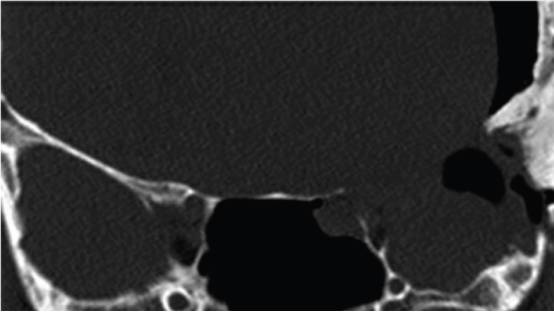

图1. 上图为一个典型的左侧外侧蝶骨嵴脑膜瘤伴骨质增生。下图为右侧蝶眶脑膜瘤伴显著的蝶骨嵴、床突和眶壁增生,导致眼球突出。为长期的控制肿瘤并改善眼球突出,有必要同期切除硬膜内肿瘤和增生的骨质。